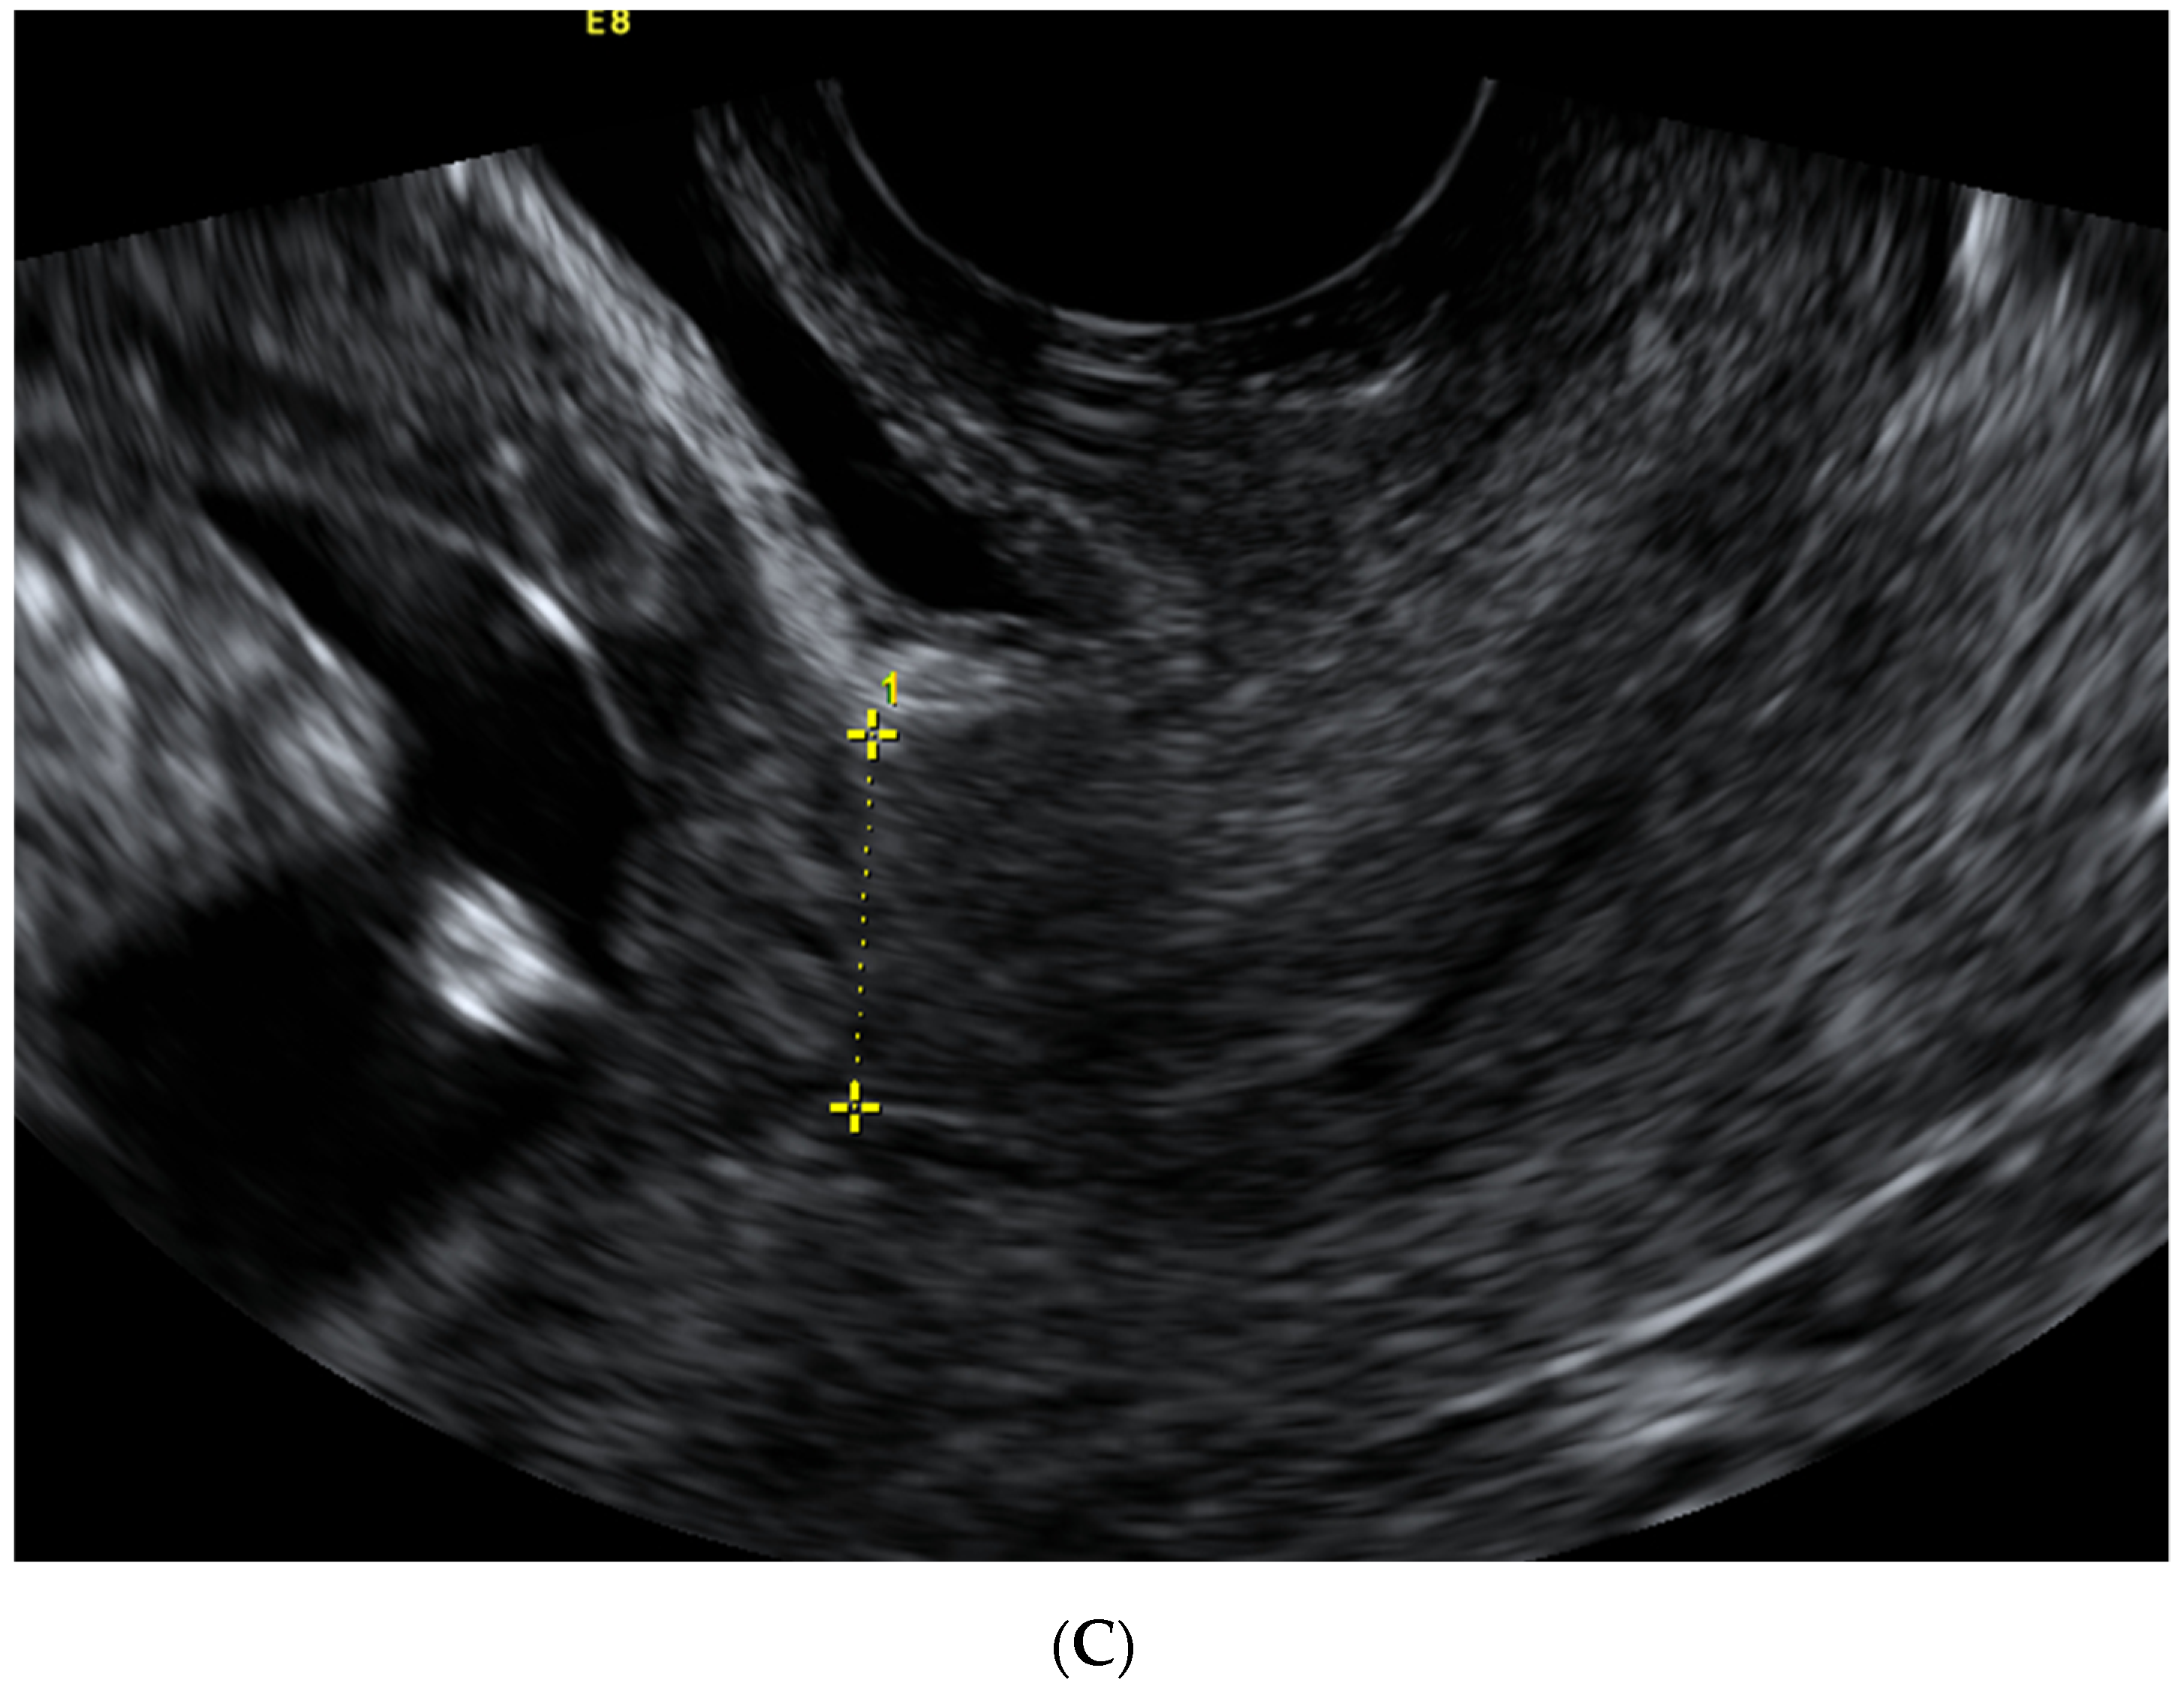

| Scar Characteristic (mm) | First Trimester Median (IQR)  | Second Trimester Median (IQR)  | Third Trimester Median (IQR)  |

|---|---|---|---|

| CS scar niche length | 5.0 (3.9–7.0) | - | - |

| CS scar niche depth | 6.9 (4.8–9.7) | - | - |

| RMT | 4.7 (3.3–5,9) | - | - |

| Myometrial thickness in the isthmus uteri | 12.7 (10.8–14.5) | - | - |